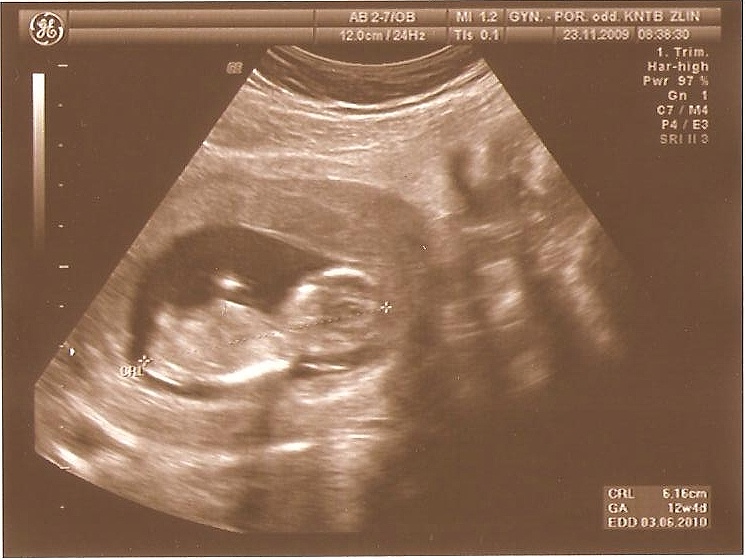

03-12+4tt CRL 6,16cm NT Screening